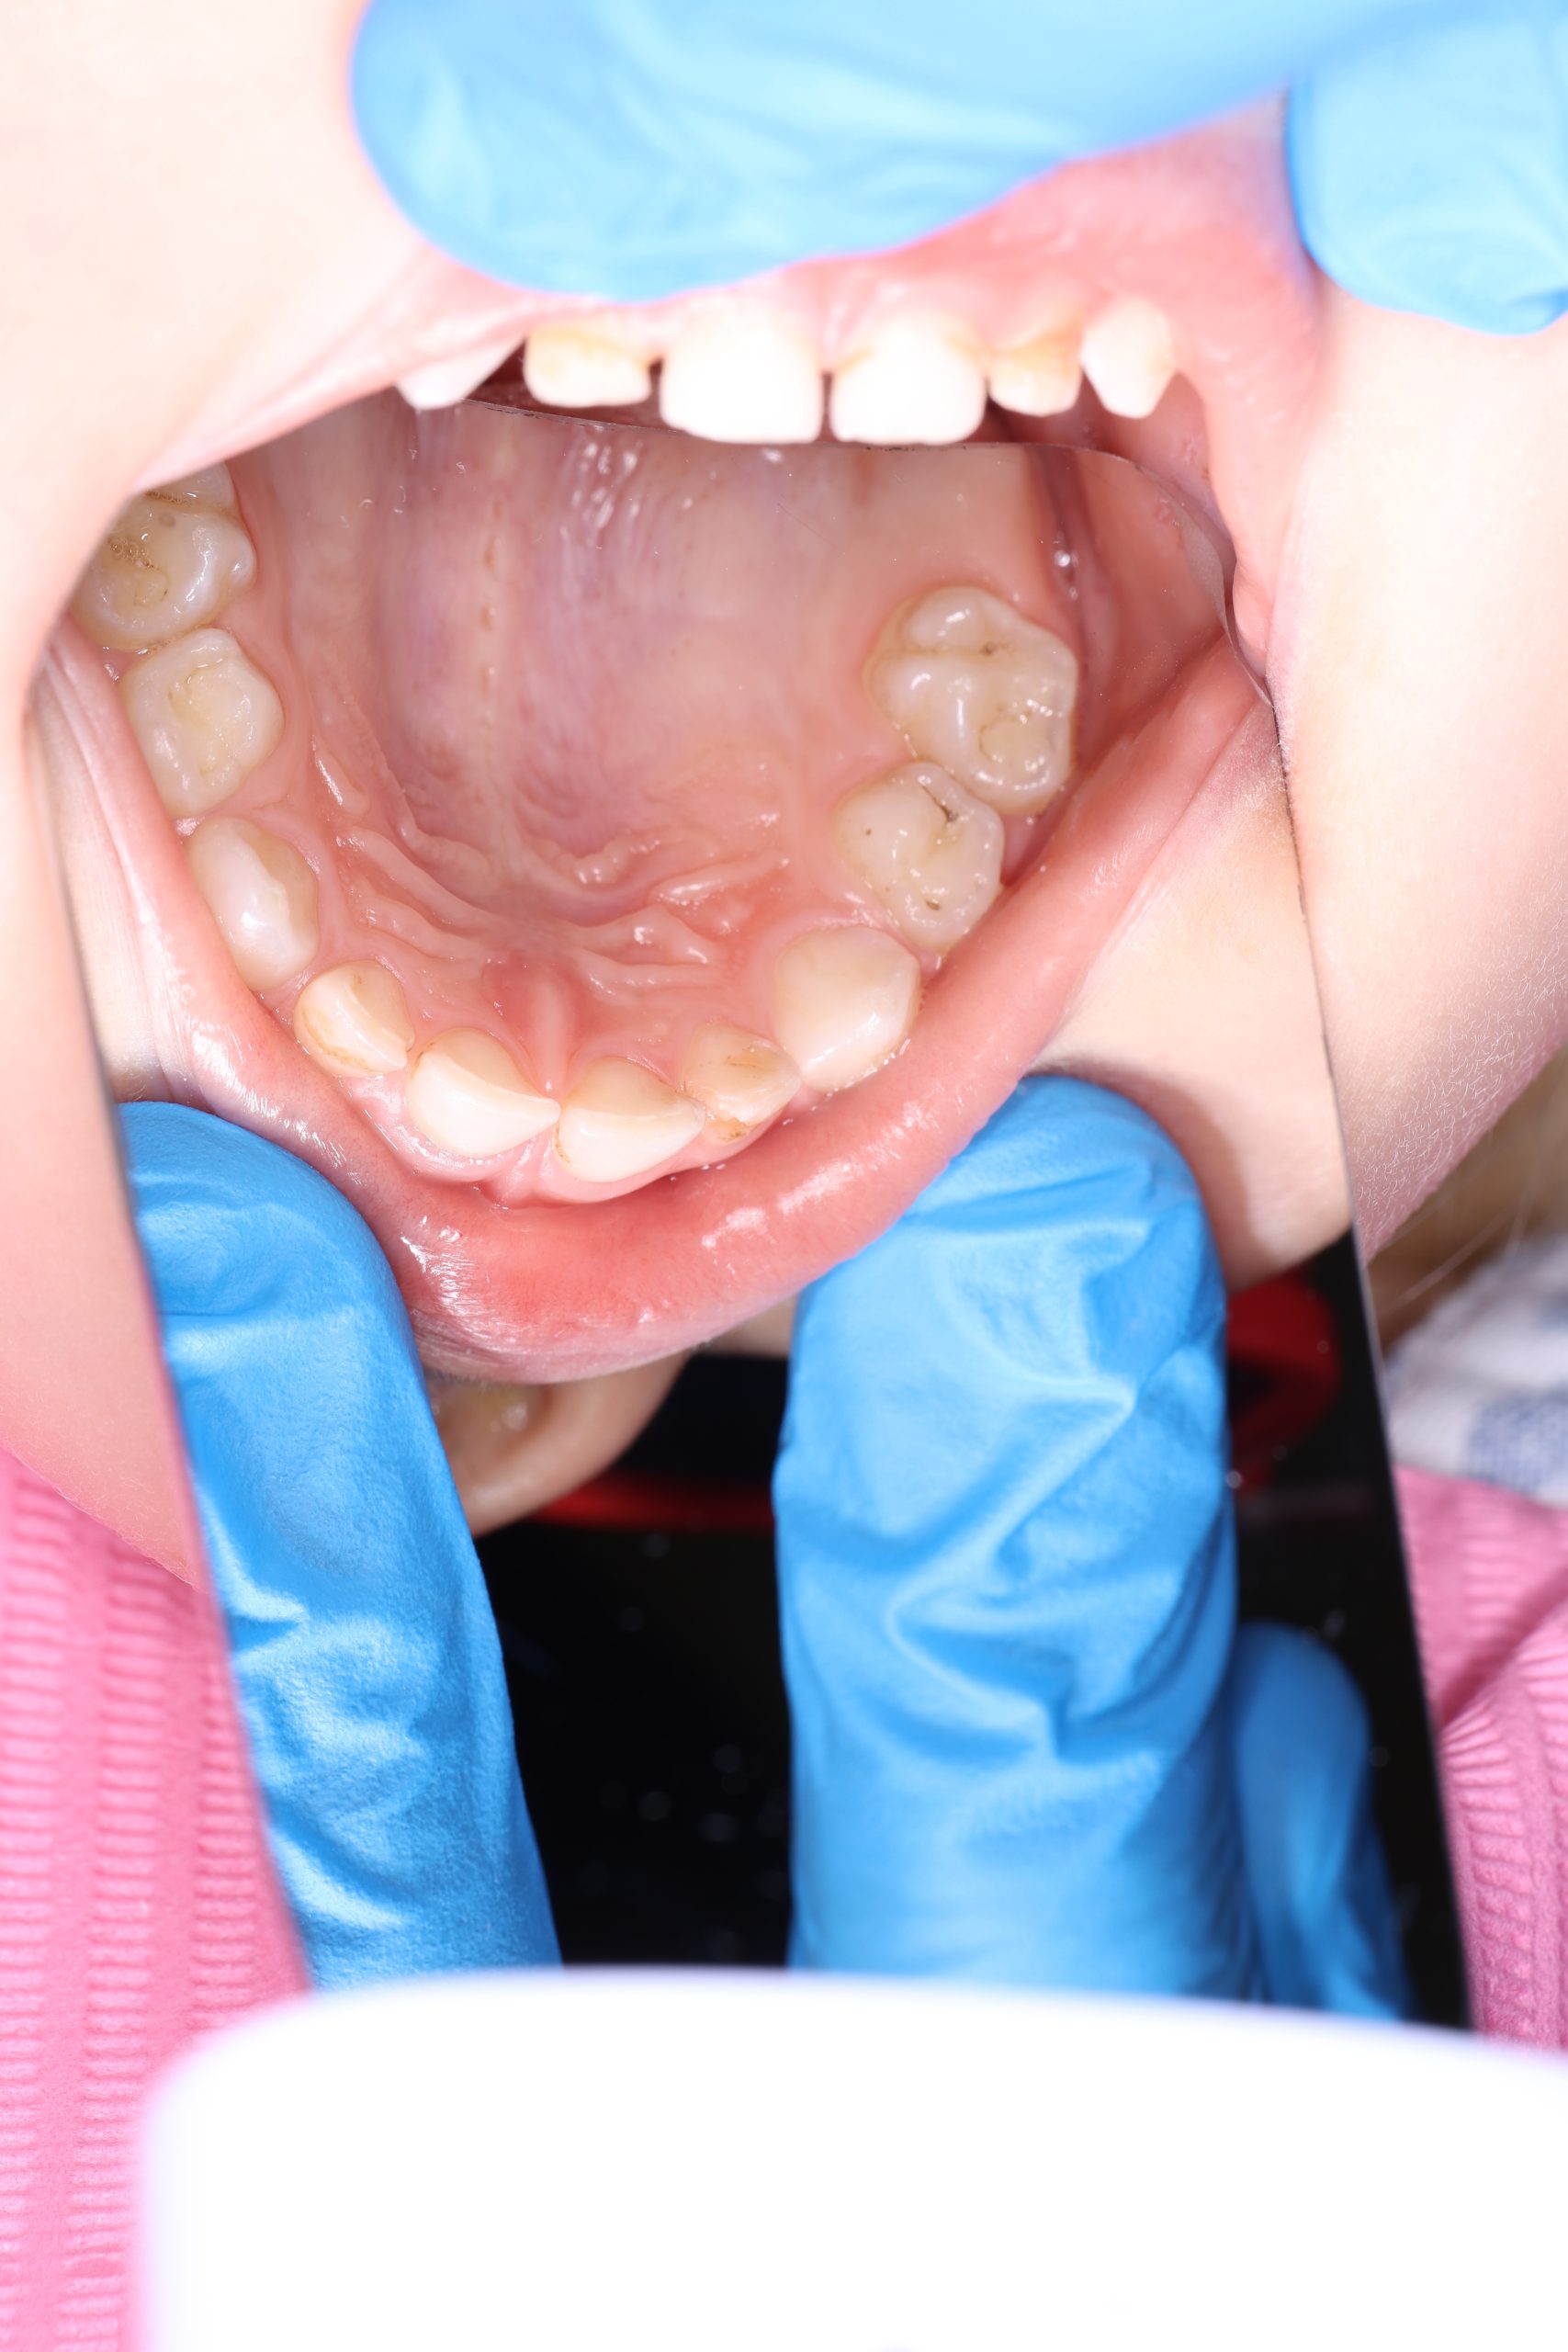

We examine the condition of teeth, gums, and bite. - Plaque Disclosure with Special Indicators

Areas that weren’t cleaned well appear purple. The darker the shade, the older the plaque. This helps both kids and parents understand where brushing needs to improve. - Brushing Training & Home Care Tools Selection